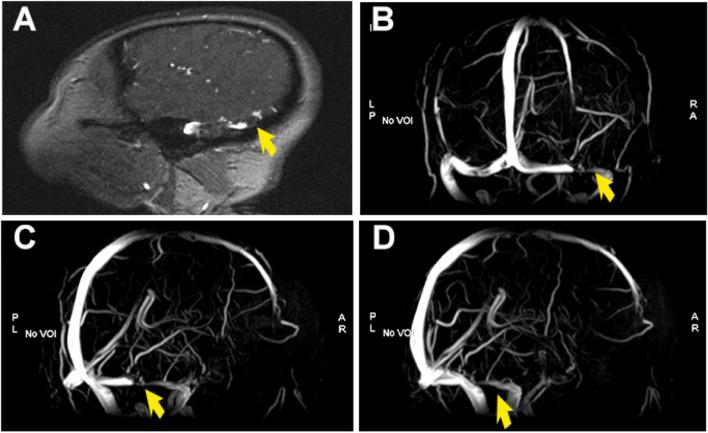

A 54-year-old male patient came to our department with a fever for 2 days and altered mental status for 1 day. Abdominal computed tomography (CT) and liver magnetic resonance imaging (MRI) revealed multiple liver abscesses. The blood culture was identified as Klebsiella pneumoniae sepsis. Head contrast-enhanced MRI and magnetic resonance venography (MRV) imaging showed multiple thrombus formation in the right transverse sinus and sigmoid sinus. The patient's infection and thrombosis were controlled within one week of multidisciplinary comprehensive treatment such as antibiotic and antithrombotic therapy, and a good clinical recovery during the 1-month follow-up.

一名 54 岁男性患者因发热 2 天伴精神状态改变 1 天来我院就诊。腹部 CT 和肝脏 MRI 显示多发肝脓肿。血培养鉴定为肺炎克雷伯菌败血症。头部增强 MRI 和磁共振静脉造影(MRV)成像显示右侧横窦和乙状窦多发血栓形成。经过多学科综合治疗(如抗生素和抗血栓治疗)一周后,患者的感染和血栓得到控制,在 1 个月的随访期间临床恢复良好。